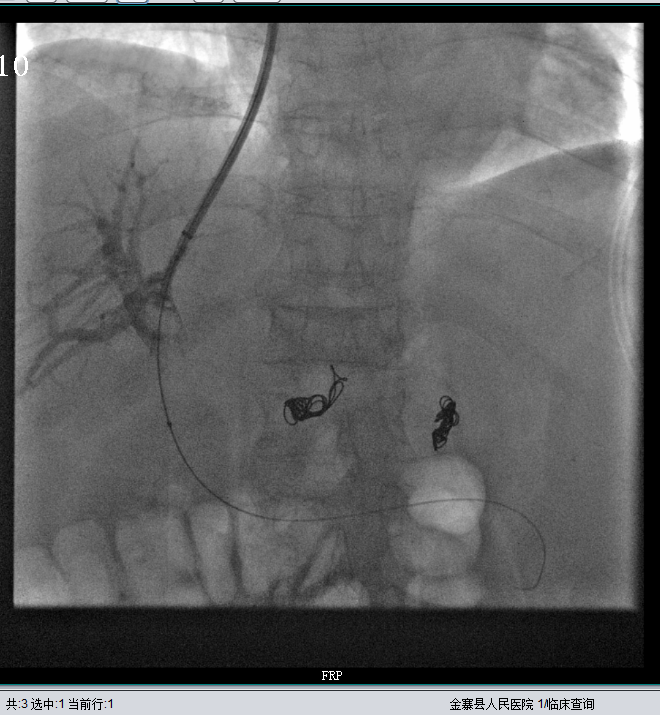

经肝静脉穿刺进入门静脉,建立分流道并显示增粗的胃冠状静脉